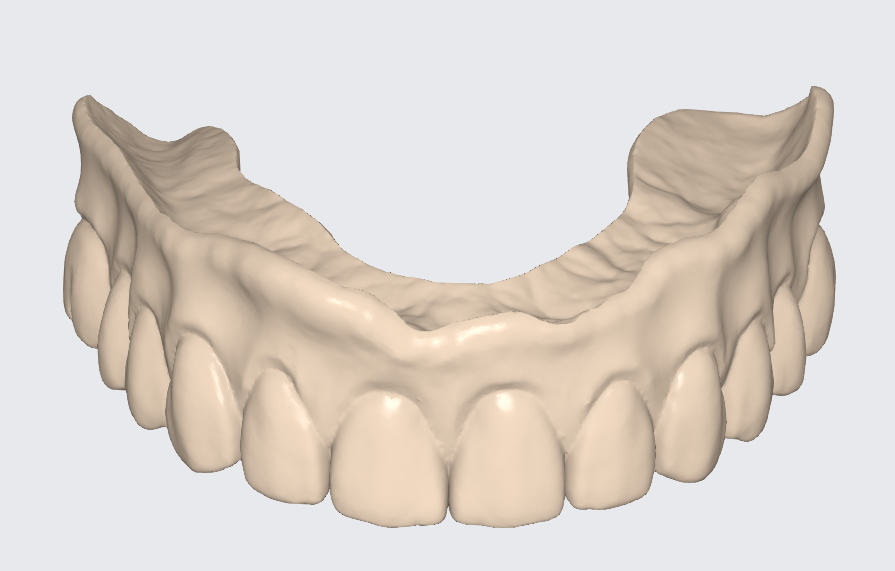

A patient presented with mobile dental bridges, significant difficulty chewing, and dissatisfaction with their overall dental esthetics. A preliminary assessment involved panoramic X-rays and intraoral scanning to evaluate dental status, bone quality, and available prosthetic space.

Using the Aoralscan Elite intraoral scanner (Shining 3D), detailed scans of edentulous ridges and interim prostheses were recorded efficiently and accurately. Edentulous arch scanning proved precise and rapid, significantly simplifying the workflow.